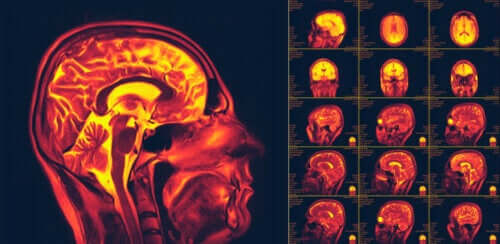

La neuroplasticité, également appelée plasticité cérébrale, est l’une des découvertes les plus importantes sur le corps humain lors de ces dernières décennies. Elle consiste en la capacité de notre cerveau à changer et s’adapter en réponse à de nouvelles conduites ou expériences.

Différents tests d’imagerie et de stimulation ont été entrepris et ont pu révéler l’existence de la neuroplasticité. Actuellement, tous les mécanismes intervenant dans ce processus sont encore en cours d’études.